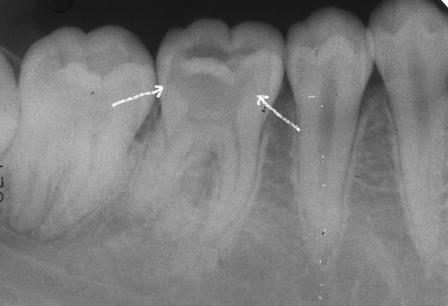

下顎7番の頬側歯茎部カリエスの原因 2025.06.04